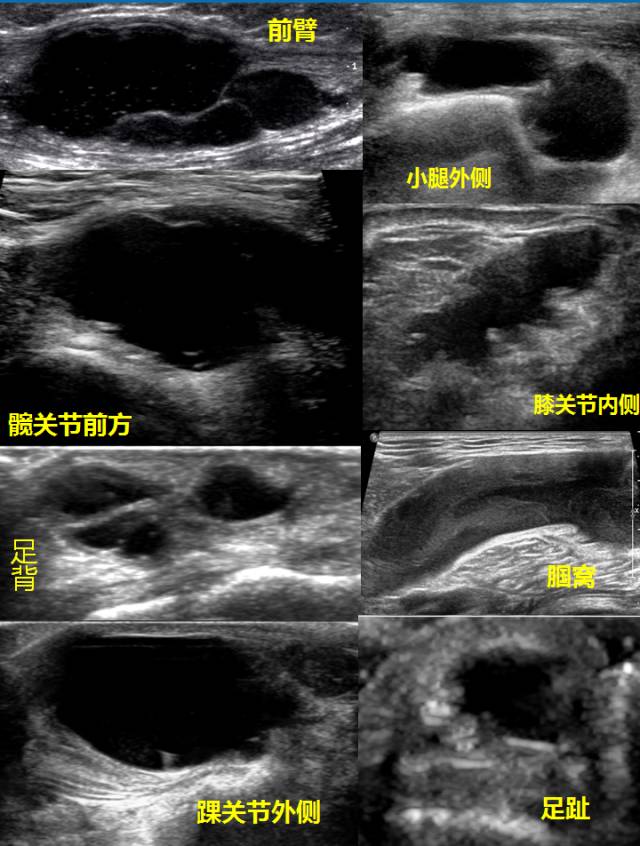

腱鞘囊肿可发生于任何年龄,多见于青年和中年,女性多于男性。囊肿生长缓慢,圆形,直径一般不超过2厘米。也有突然发现者。少数可自行消退,也可再长出。部分病例除局部肿物外,无自觉不适,有时有轻度压痛。多数病例有局部酸胀或不适,影响活动。

检查时可摸到一外形光滑、边界清楚的圆形肿块,表面皮肤可推动,无粘连。囊肿多数张力较大,肿块坚韧,少数柔软,但都有囊性感。囊肿的根基固定,几乎没有活动。B超检查可帮助确定肿块的性质。

超声:一般表现为皮下层、与肌腱或关节关系密切的类圆形或不规则无回声结节,可单房,也可分隔,边界清楚,后壁回声增强,较大囊肿囊壁上可探及血流信号。